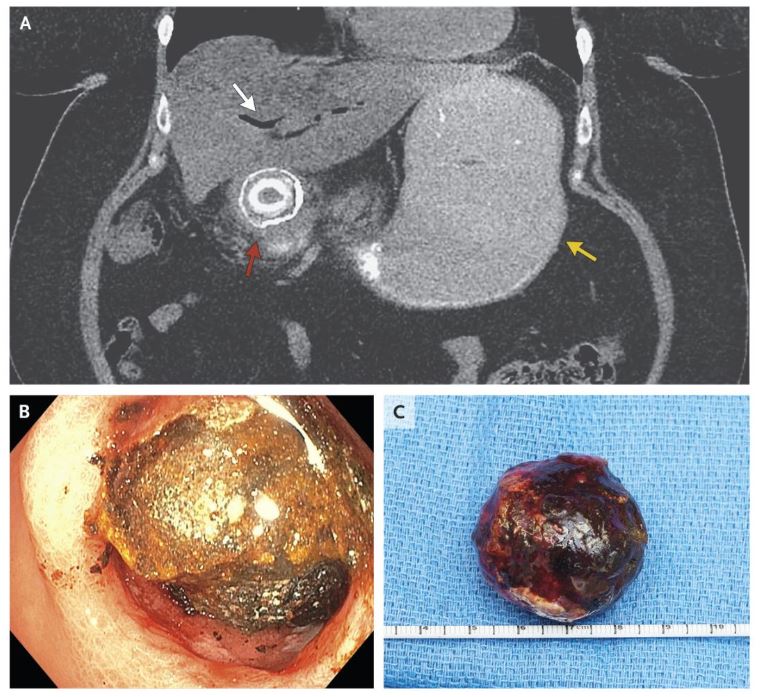

CT显示胆道积气(白箭头处),胃扩张(黄箭头处),十二指肠近端胆结石梗阻(红箭头处);

尝试进行内镜下机械碎石术取石(图B),但失败了,并因十二指肠近端穿孔而复杂化;

之后进行开腹手术以修复十二指肠穿孔并切除混合胆结石,其最大直径处4.4cm(图C);